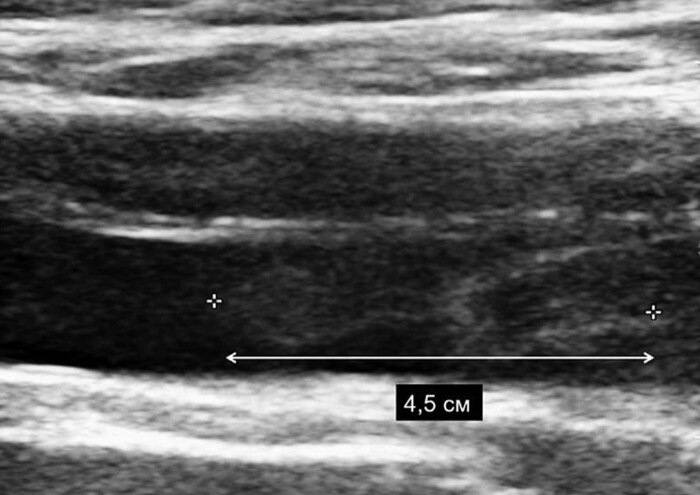

Ко мне на амбулаторный приём обратился пациент 40 лет с жалобами на увеличение в объёме левой нижней конечности. Нога ниже колена стала отекать пару недель назад, особенно после бега, а бегает он каждый день. Провоцирующий фактор выявить не удалось, получается "на ровном месте". Травм не было, длительных перелётов тоже. Пациент спортсмен, бегает марафоны, правильно питается, не имеет лишнего веса и вредных привычек, не принимает никаких препаратов на постоянной основе. Так же отмечает, что в последнее время появилась одышка при привычной физической нагрузке (плохой звоночек). При осмотре меня насторожила синюшная, отёчная голень, болезненная при пальпации (ощупывании руками). Приглашаю на УЗИ, ставлю датчик в проекции глубоких вен, и сразу бросается в глаза огромный тромб от голени почти до паха, болтающийся в просвете вены. Боюсь лишний раз надавить датчиком, чтобы от тромба не оторвался кусок и не полетел в лёгкие. (У каждого есть история, где у какого-то знакомого тромб "оторвался"). Крайне неприятная ситуация и для пациента и для врача. Удивляюсь, как пациент с таким огромным тромбом бегал ежедневно, ведь любая из этих пробежек могла стать для него последней. Говорю, что с такой картиной нужна госпитализация, пациент отказывается, ведь ничего особо не болит! Объясняю, что в любой момент может случиться "отрыв" и Бог знает, чем это закончится. Всё-таки всеми правдами и неправдами удаётся убедить молодого мужчину, что нужно ехать в больницу. Вызываю 103, бригада через 10 минут на пороге клиники, без разговоров забирают.

Флотирующая (плавающая) часть в просвете вены*